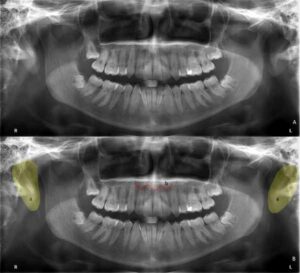

歯科X線写真における正常な解剖学_図28